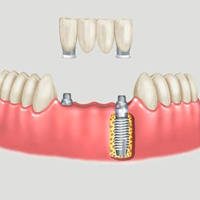

√ Prótese sobre Implante: São as próteses que podem substituir um ou mais dentes perdidos, sendo apoiados em implantes que são feitos de titânio e tem o formato de um parafuso, substituindo a raiz de um dente perdido, funcionando como raiz artificial onde será instalada a prótese por cima. É a melhor alternativa para o uso de prótese, pois apresenta as seguintes vantagens: Conservação dos dentes vizinhos por não precisar desagastá-los; preservação do volume ósseo por manter um estímulo contínuo e facilidade de higienização.